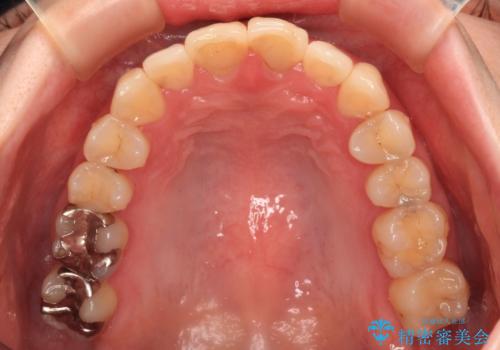

変色した前歯 オールセラミッククラウンにより審美歯科治療

- 神経を取り除いたことで経年変色した前歯2本を気にして来院された患者様です。

根管治療を行う必要はないと判断し、双方の歯にグラスファイバーを含有した土台を植立してオールセラミッククラウンにて補綴することとしました。

色調が周囲の歯とアウトともに、表面のつぎはぎや穴を封鎖した際の段差などが解消され、天然歯のような感触となりました。